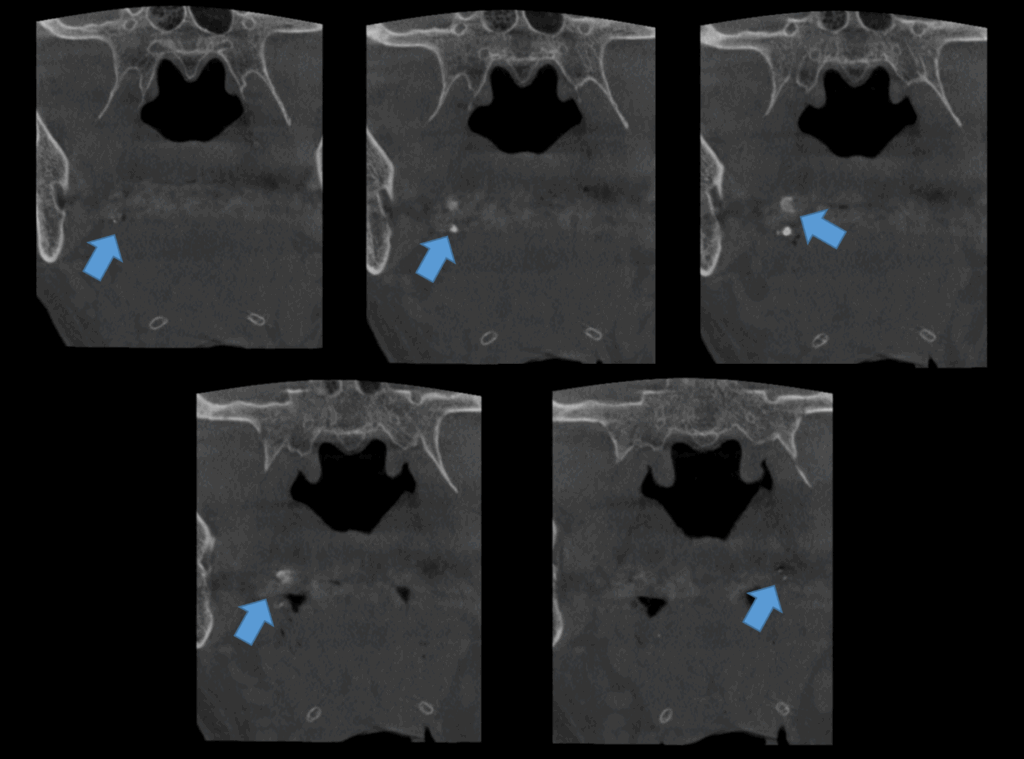

A la evaluación de la tomografía de campo mediano se observan dichas imágenes hiperdensas múltiples, de forma irregular y densidad cálcica en el espacio parafaringeo, a predominio del lado derecho. Signos imagenológicos compatible con cálculos amigdalinos o tonsilolitos.

CORTES CORONALES